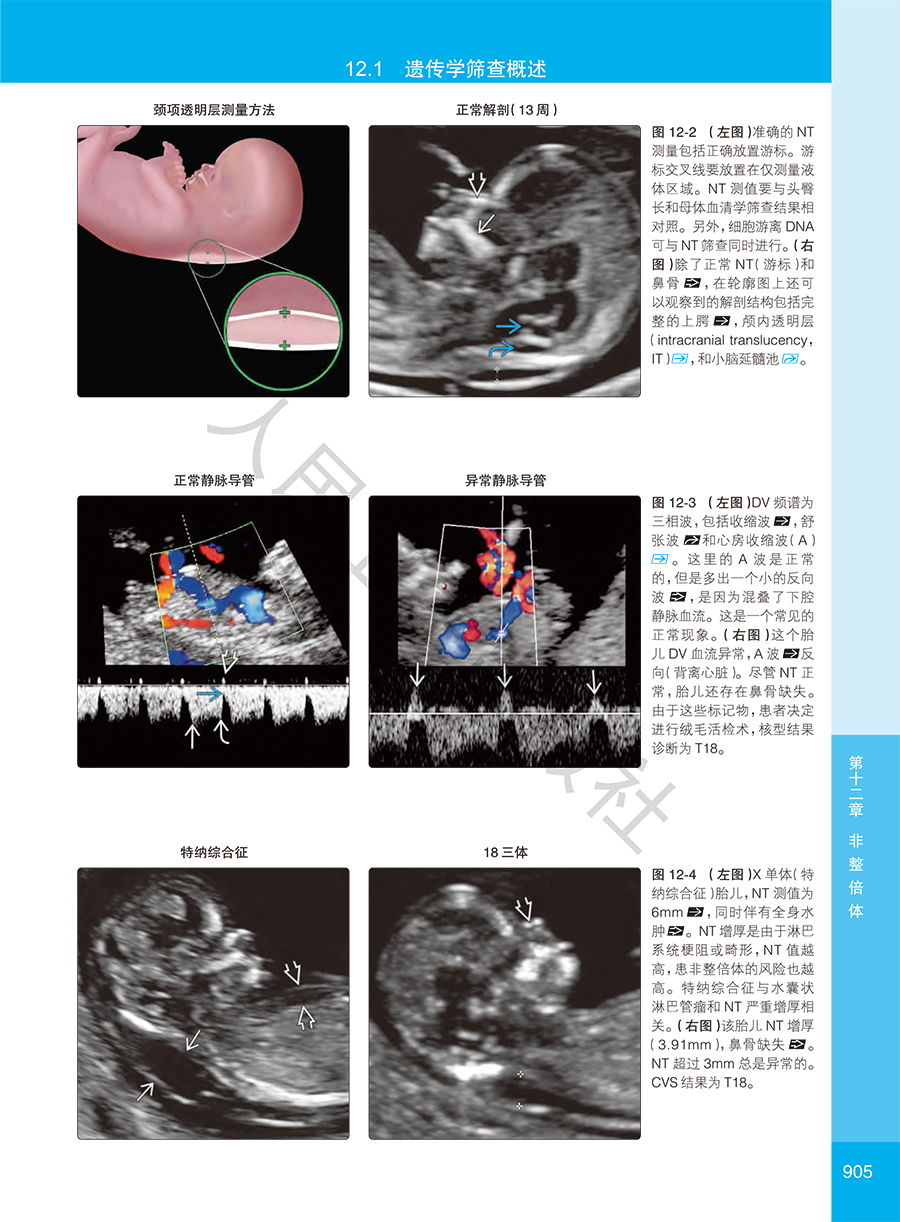

本书是美国妇产学会针对产科影像诊断从业人员专业提升编写的围生期诊断与筛查高级参考图库,专科医师培训的优秀教材。全书共16章314节,用5000多幅精美照片详细图解了胎儿大脑、脊柱、面部和颈部、胸、心脏、腹壁、胃肠道、泌尿生殖系统、肌肉骨骼、脐带、胎盘和胎膜在孕早、中、晚期的正常与常见异常情况的经典影像特征和相关鉴别论断,并对多胎妊娠、染色体异常、综合征和多系统疾病、感染性疾病等特殊状况的早期诊断进行了经验独到的讲解,对孕期母体相关疾病的影像论断与鉴别也进行了专门论述。